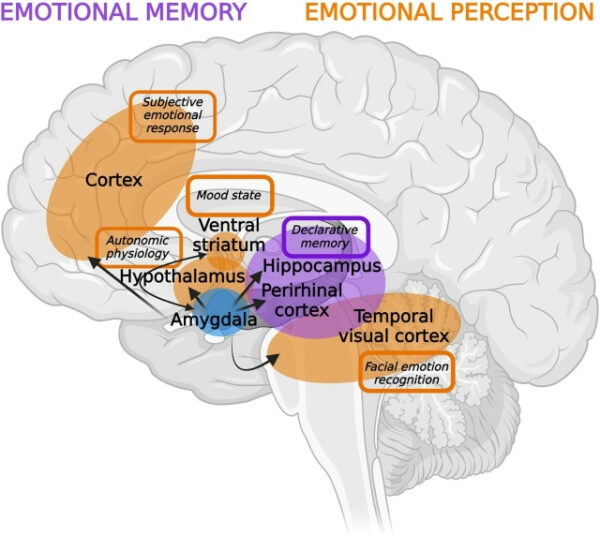

Эти исследования позволяют выявить общие закономерности среди субъективных отчетов, а также физиологических и нейронных маркеров, таких как локальные полевые потенциалы, записи одиночных нейронов, вегетативная реактивность и метрики отслеживания взгляда. В совокупности эти данные предоставляют взаимодополняющие доказательства того, что человеческая миндалина выполняет многогранную роль как в текущем эмоциональном переживании, так и в кодировании и извлечении воспоминаний о прошлом.

На первой иллюстрации показано широкое влияние человеческой миндалины на поведение и выделена сеть потенциальных терапевтических мишеней для клинической нейромодуляции. Области, выделенные оранжевым цветом, представляют зоны, участвующие в регуляции миндалиной текущего эмоционального восприятия и настроения. Области, выделенные фиолетовым цветом, представляют зоны, критически важные для влияния миндалины на воспоминания о прошлом опыте. Широкая вовлеченность миндалины в вегетативную физиологию, субъективные эмоциональные реакции, распознавание эмоций, декларативную память и регуляцию настроения делает ее многообещающей мишенью для будущих приложений клинической нейромодуляции.

Однако, учитывая широкомасштабное влияние миндалины на множество нейронных систем, будущим исследованиям необходимо тщательно учитывать трудности воздействия на эту область и окружающую ее сеть с достаточной точностью, чтобы минимизировать непреднамеренные эффекты и неблагоприятные исходы.